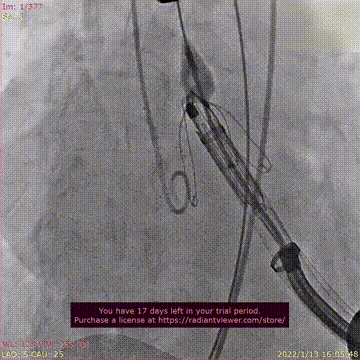

瓣膜释放过程

术后DSA影像图